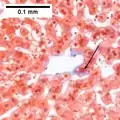

The primary characteristic of MASLD is the accumulation of lipids in the liver, largely in the form of triglycerides.[19] However, the mechanisms by which triglycerides accumulate and the reasons that accumulation can lead to liver dysfunction are complex and incompletely understood.[19][47][48] MASLD can include steatosis along with varied signs of liver injury: either lobular or portal inflammation (a form of liver injury) or ballooning degeneration. Similarly, NASH can include histological features such as portal inflammation, polymorphonuclear cell infiltrates, Mallory bodies, apoptotic bodies, clear vacuolated nuclei, microvesicular steatosis, megamitochondria, and perisinusoidal fibrosis.[16] Hepatocyte death via apoptosis or necroptosis is increased in MASH compared with simple steatosis, and inflammation is a hallmark of MASH.[32]

NASH (inflammation) and fibrosis stage 1

NASH (inflammation) and fibrosis stage 1 NASH (inflammation) and fibrosis stage 2

NASH (inflammation) and fibrosis stage 2 Lobular inflammation

Lobular inflammation

NAFLD comprises two histological categories: NAFL, and the more aggressive form NASH. The presence of at least 5% fatty liver is common to both NAFL and NASH, but the features of substantial lobular inflammation and hepatocyte injuries such as ballooning or Mallory hyaline only occur in NASH. The majority of NAFL cases show minimal or no inflammation.[3][5][7] Pericentral and perisinusoidal fibrosis occur more often in adult-onset NASH, whereas portal fibrosis is more common in children with the disorder. NASH represents a more advanced stage of NAFL and is associated with poor outcomes such as cardiovascular events, cirrhosis, or hepatocellular carcinoma. ICD-11 does not use the term NAFL as it was deemed confusing with the family of disorders NAFLD. The preferred descriptions are instead: MAFLD without NASH or simple steatosis and "NASH". Also, the modifier with or without fibrosis or cirrhosis completes the diagnostic description.[3][7]